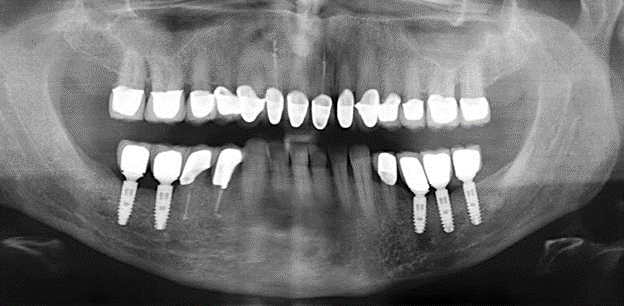

A 52-year-old patient presented in our clinic for the first time in 2004 following tooth loss in the third quadrant, expressing a desire for a new prosthetic restoration. Periodontal and radiological diagnostics revealed the need for extensive periodontological treatment. In addition, teeth 48, 28 and 27 were attributed a very poor prognosis and were subsequently extracted (Fig. 1). Following the successfully completed, systematic periodontological treatment, a fixed dental implant was inserted with the introduction of five implants in tooth regions 35, 36, 37, 46 and 47. Prosthetic treatment of the natural teeth was effected with veneered zirconium dioxide ceramic crowns; the implants were composed of two-piece, individual zirconium dioxide abutments and similarly veneered crowns made of a zirconium dioxide ceramic (Cercon base colored, Dentsply Sirona Lab). Definitive insertion of the prosthetic restoration occurred in 2005.

Due to the presence of periodontal disease, SPT was performed every three months in the first years following the insertion. The patient demonstrated a high degree of motivation and good compliance. The pocket depths recorded annually revealed a stable periodontal situation with a BOP index of below five per cent. On the basis of the stable periodontal situation and good cooperation on the patient’s part, the recall interval was extended to every six months as of the sixth year of the prosthetic function phase. Following the change in the recall interval, the respective annual documentation of the periodontal status continued to reveal a stable periodontal situation with no increase in the pocket depths and a BOP index below five per cent (Fig. 2a and b).

The ten-year check-up revealed no indications of advancing clinical attachment loss or peri-implant bone substance loss (Fig. 3).